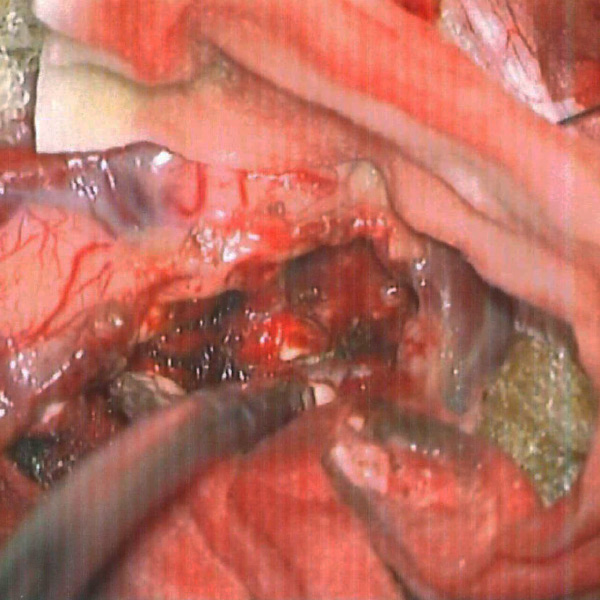

'19年5月

30代

富永/久貝

右中小脳脚 出血再発

SM 3(S1,E1,V1)

米国の病院

No.359 モニタリング

No.359 手術前

No.359 手術中

No.359 手術後

出血既往があり。2回の手術前血管内手術の後に、

Lateral transpeduncular approachにより再々出血予防を目的に

摘出手術を行う。完全摘出であることを確認した。

手術による合併症や後遺症なしで退院した。経過良好。